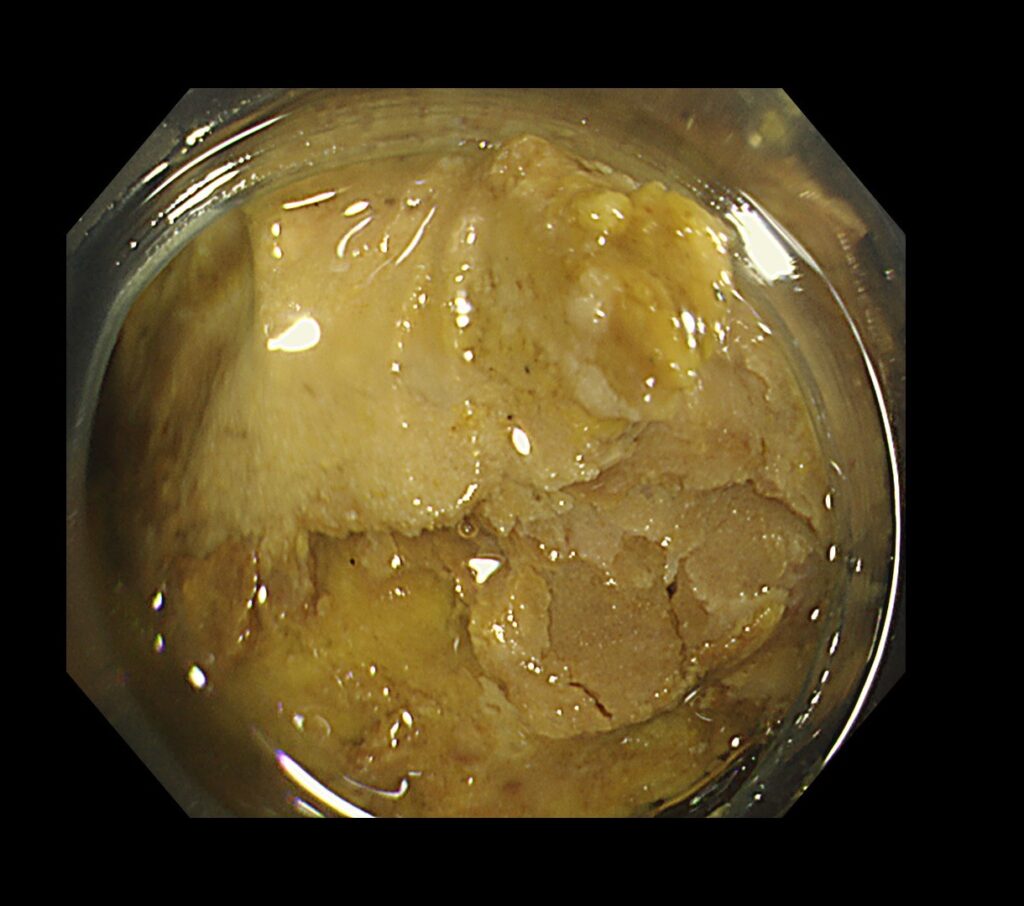

糞石を内視鏡処置具で破砕していくと、何層にも重なり合う便の層を認めました。

翌日・翌々日、腸の蠕動を促す点滴を行い、腸閉塞・腸麻痺を解除し、手術の回避ができた一例です。